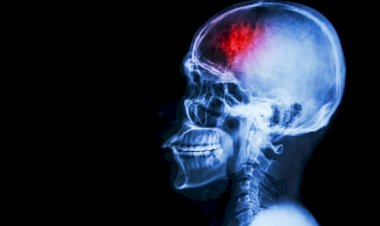

Médicos afirmam que Covid causou derrame em adolescente...

Especialistas acreditam que coronavírus pode ter causado um acidente vascular cerebral...